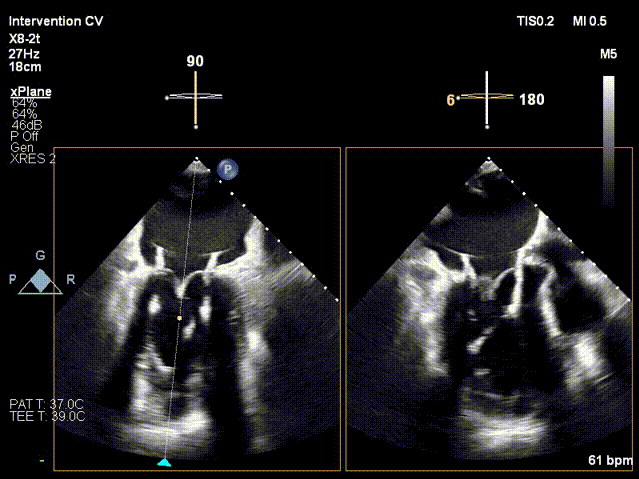

手术采用左侧第五肋间微创切口入路,超声引导下经心尖将导丝置入左房,送入瓣膜输送系统,经过一系列超声定位后逐渐释放瓣膜。确认瓣膜位置满意后撤出输送系统,瓣架恢复膨胀完全、锚定良好,人工二尖瓣瓣叶形态完好,无反流及无瓣周漏,人工二尖瓣峰值流速1.10m/s、平均压差2mmHg,峰值压差5mmHg,由连续多普勒据PHT估测面积约3.5cm²,左室流出道无梗阻,峰值流速0.76m/s。术中出血约100ml,无输血,术后患者安全返回监护室。

TMVR术前

TMVR术中